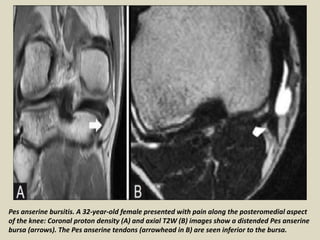

Pes anserine bursitis. A 32-year-old female presented with pain along the posteromedial aspect

of the knee: Coronal proton density (A) and axial T2W (B) images show a distended Pes anserine

bursa (arrows). The Pes anserine tendons (arrowhead in B) are seen inferior to the bursa.